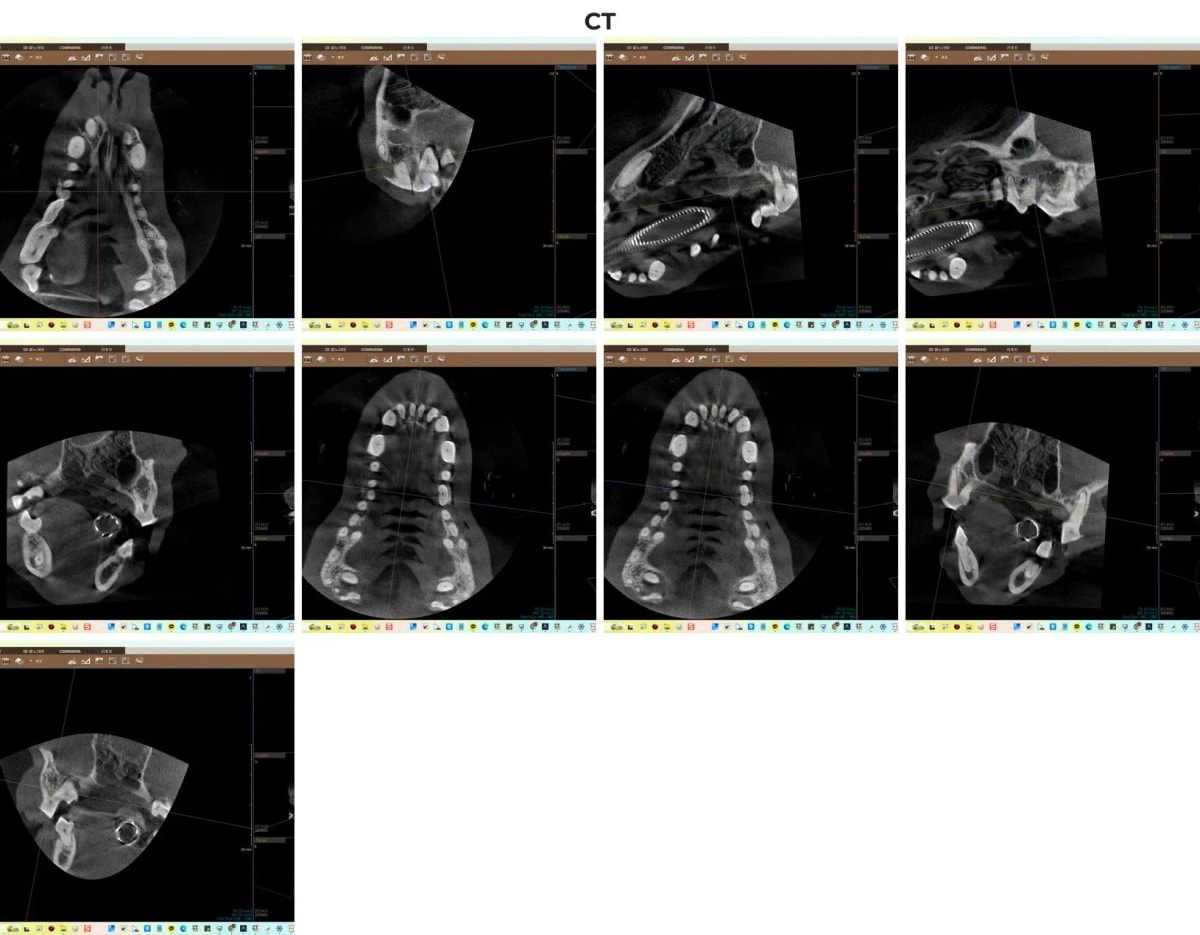

ℹ️ 치과 CT의 중요성

치아 뿌리에 숨겨진 염증과 잇몸뼈(치조골)가 얼마나 얇아졌는지를 정확히 파악하기 위해서는 3차원 입체 영상이 필수적입니다. 금호동물병원은 광주 전남 유일 동물전용 치과 CT를 보유하여 육안이나 평면 엑스레이로 놓치기 쉬운 미세 병변까지 완벽하게 진단합니다.

광주 전남 유일 치과 CT를 통한 행복이의 치조골 흡수 진단 영상

CT 검사와 더불어 구강 방사선(X-ray) 촬영을 진행한 결과, 행복이의 치주염은 매우 심각한 단계였습니다. 상하악 다수의 앞니와 작은 어금니 주변의 잇몸뼈가 심하게 녹아내려 치아 흔들림이 극심했고, 치아 406, 411번은 이미 자연 소실(Missing)된 상태였습니다.